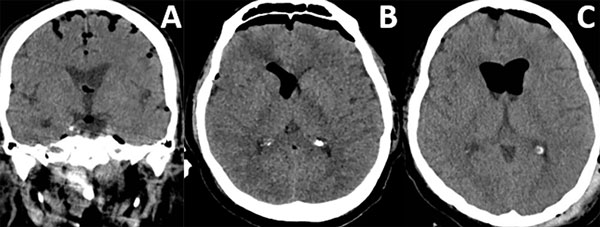

Patrones y grados de NE: NE subdural (Figura 1), se clasificó en 3 grados: leve (menor al espesor óseo), moderado (entre una vez y dos veces el espesor óseo) y severo (dos o más veces el espesor óseo). NE subaracnoideo (Figura 2), se clasificó en 3 grados: leve (confinado a cisternas basales), moderado (cisternas supratentoriales predominio unilateral), severo (generalizado). NE ventricular (Figura 3), se clasificó en: leve (en IV y/o III ventrículo), moderado (alcanzó VL), severo (alcanzó y dilató los VL).

Figura 3. Neumoencéfalo ventricular. A) Leve. B) Moderado. C) Severo.